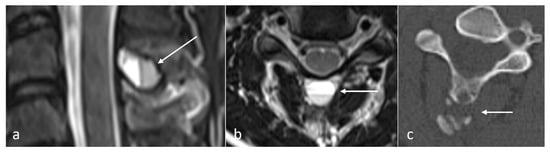

Figure 4.

Sagittal T2 (a), axial T2 (b) and axial CT (c) images demonstrating an aneurysmal bone cyst of a cervical spinous process (white arrows). Note the lytic osseous destruction on CT and the characteristic presence of fluid–fluid levels on MRI.